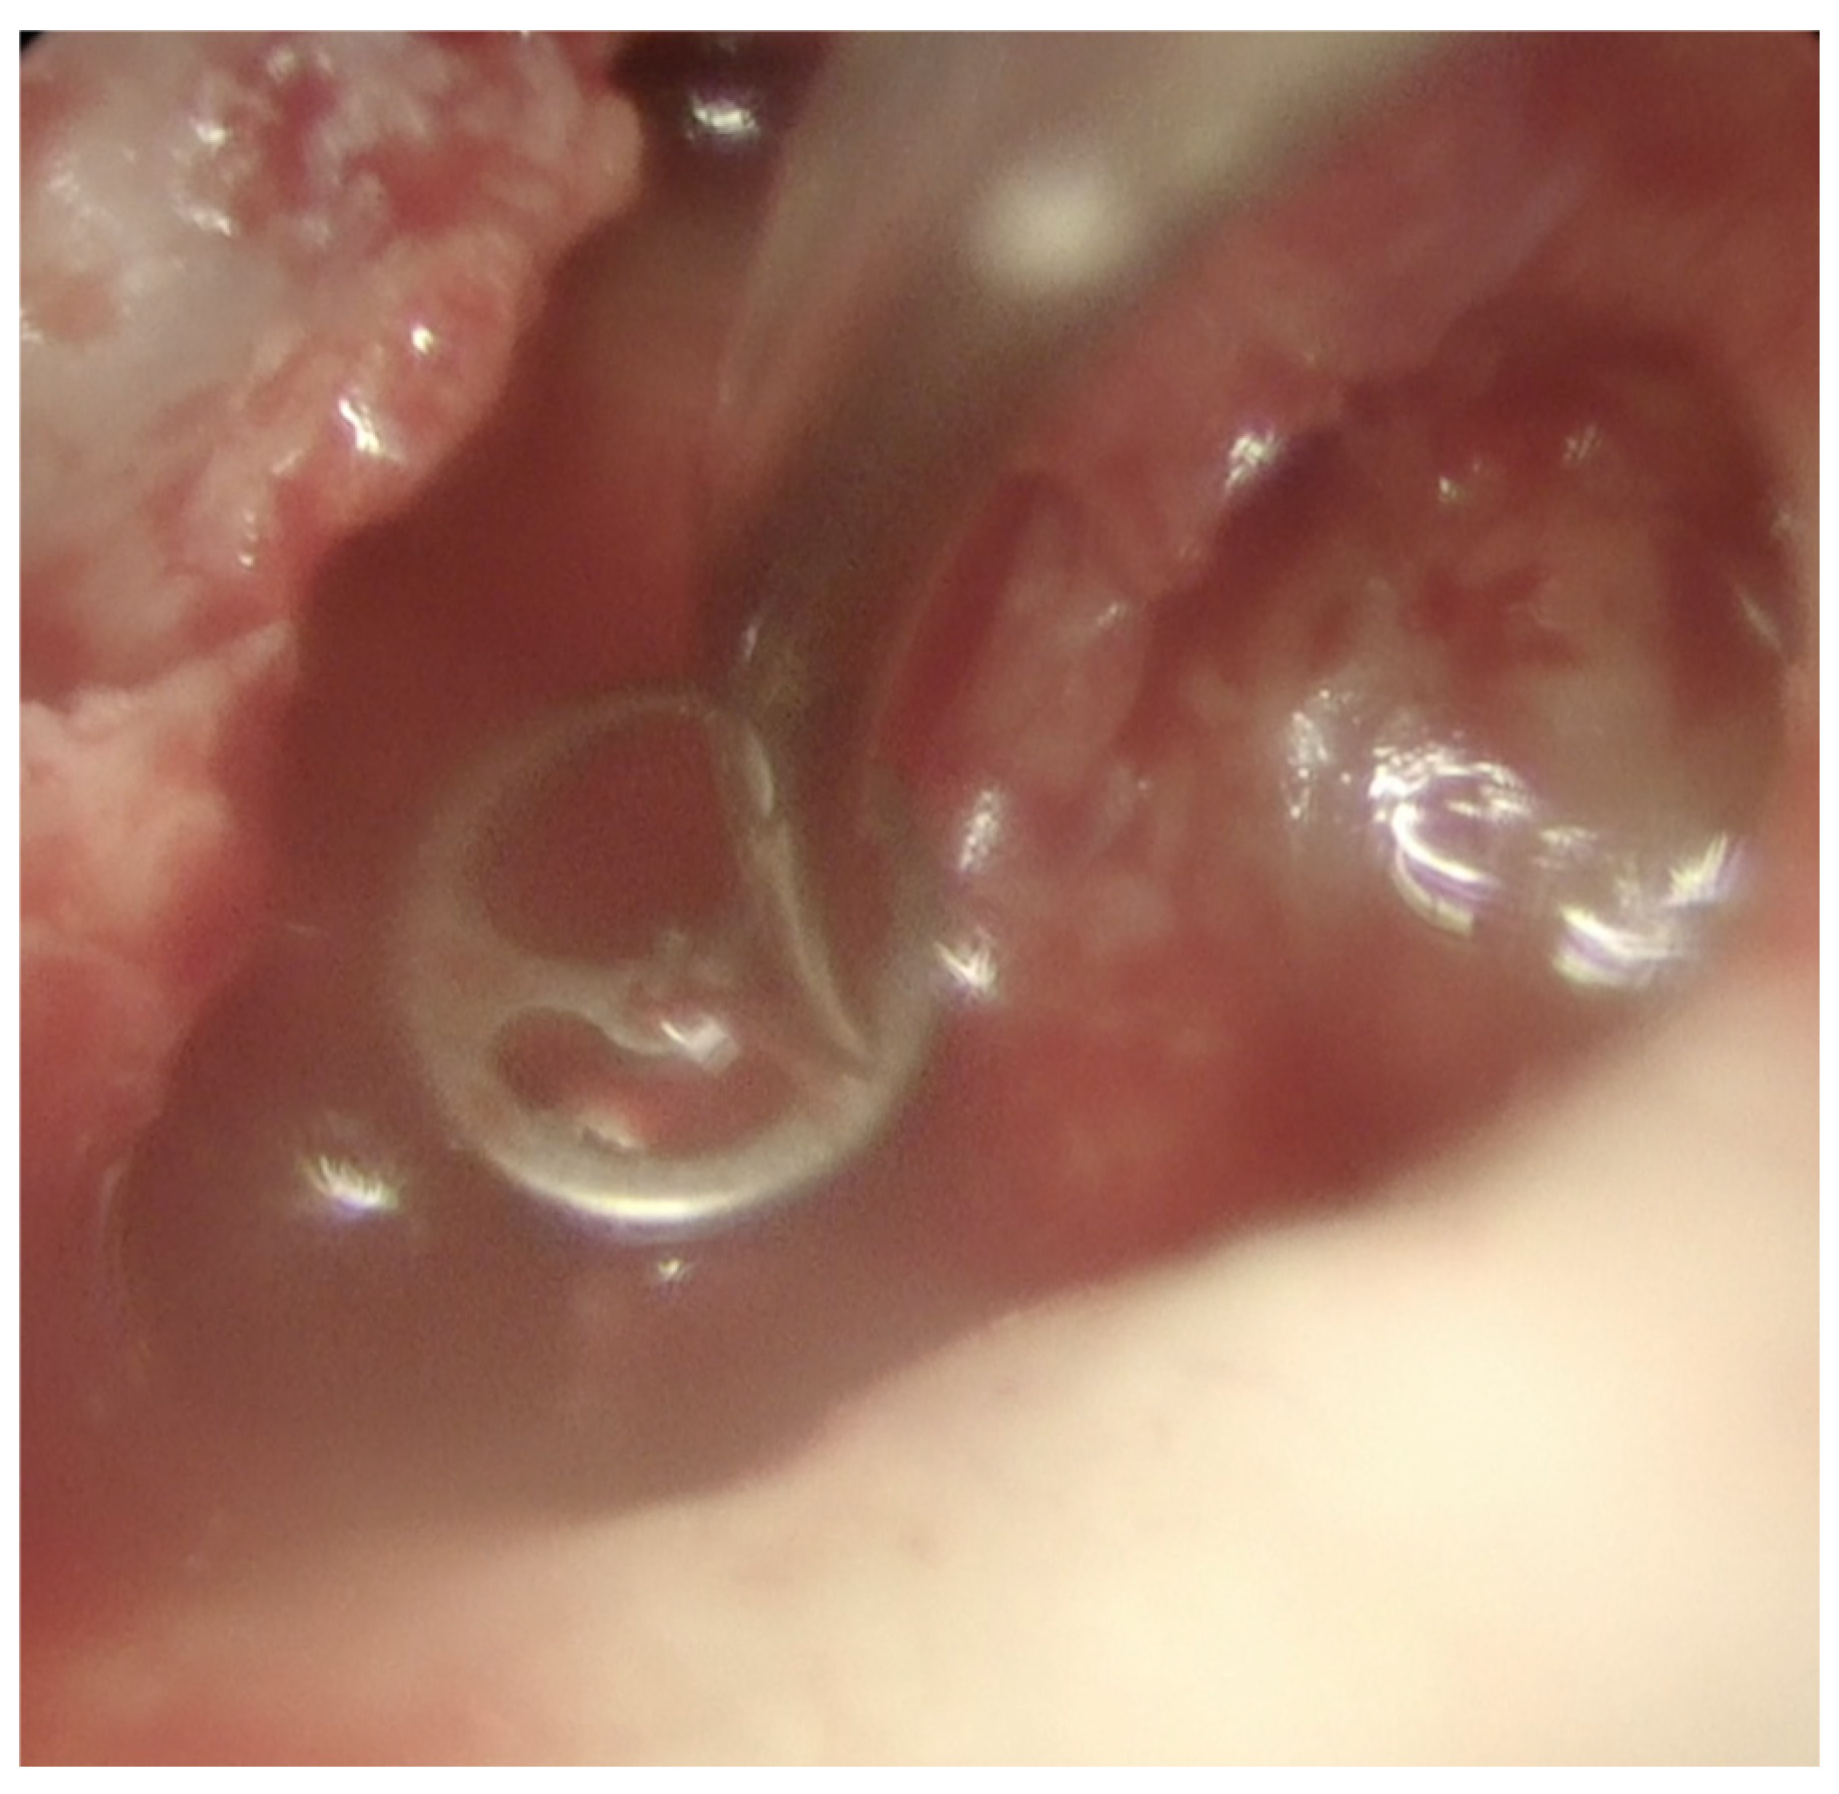

Examination revealed a superior perforation with keratin within (Figure 1a). The remaining drum was opacified consistent with previous graft reconstruction and/or tympanosclerosis.

Figure 1a. Endosopic view of left tympanic membrane showing attic perforation.